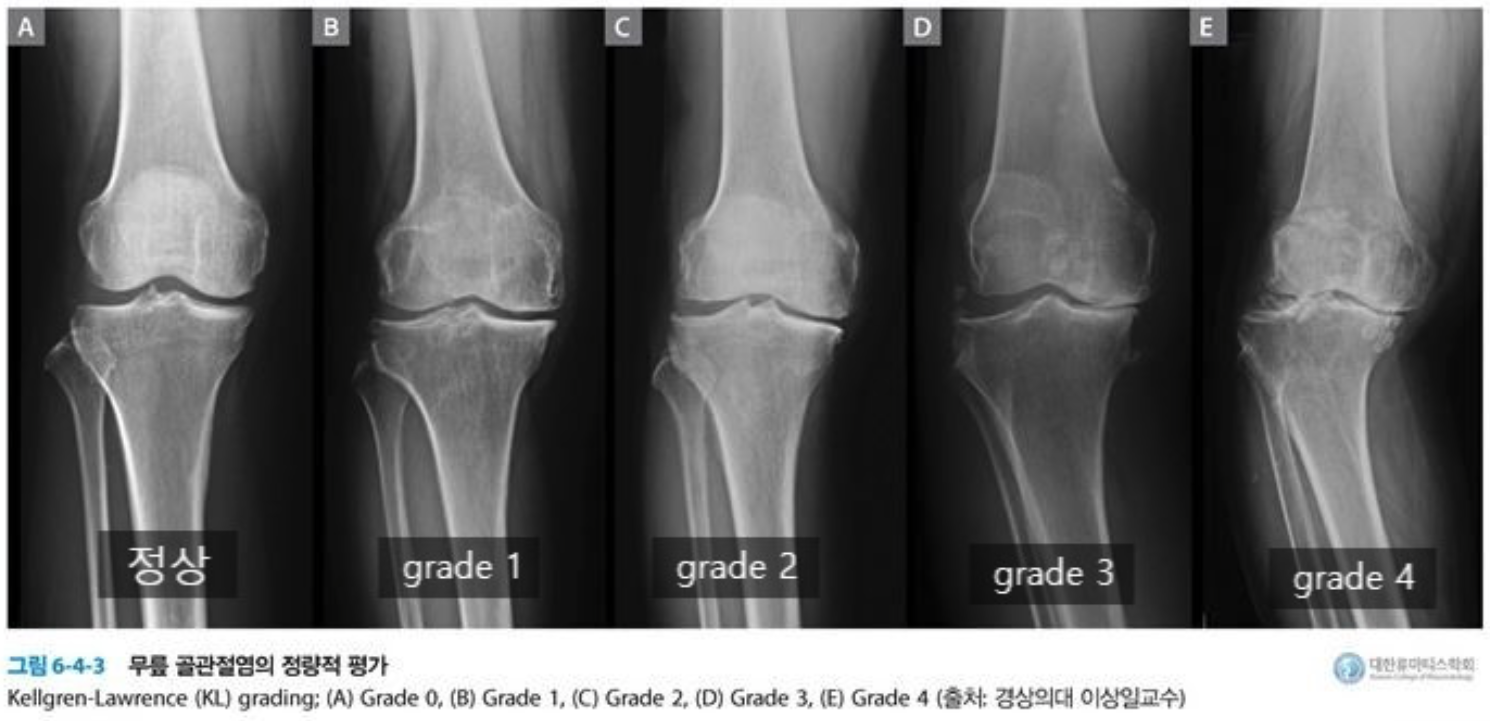

무릎 연골주사는 무릎 퇴행성 관절염 초기-중기단계인 K-L grade 1-3 (Kellgren-Lawrence)에 해당하는 환자에게 투여가 가능합니다.

잔존하는 관절연골의 마찰계수를 낮춰 퇴행성 관절염 진행속도를 낮추고 통증을 감소 시키는 효과를 얻을 수 있지만, K-L grade 4에 해당하는 심한관절염은 의료보험 상 적응증의 해당하지 않기 때문에 비용이 본인부담이며, 주사의 효과가 미미하여 개선을 크게 기대하기 어렵습니다.

| 단 계 | 단계별 설명 |

| 정상 | 방사선 사진 (X-ray)상 특별한 이상이 없을 때 |

| 1 단계 | 경미한 관절공간의 협착이 관찰되고 골극이 형성되는 단계 |

| 2 단계 | 진행된 관절공간의 협착과 확실한 골극이 보이는 단계 |

| 3 단계 | 중증도의 관절공간의 협착 및 골극이 보이는 단계 연골하골의 경화 및 뼈의 변형이 발생 |

| 4 단계 | 관절공간의 현저한 협착 및 골극이 보이며 연골하골의 심한 경화와 뼈와 다리의 변형이 확인되는 단계 |